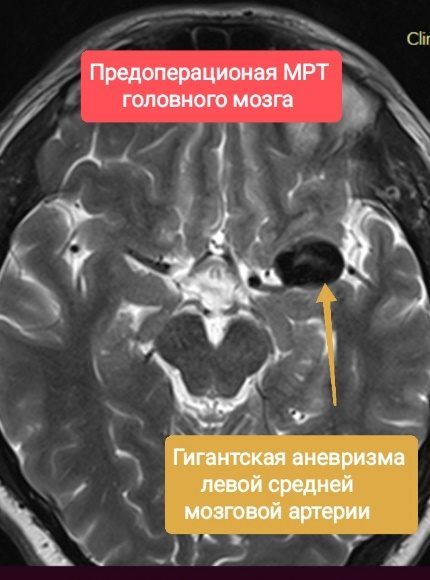

Краткая информация о пациенте: мужчина 1986 г.р. При обследовании по поводу онемения левой нижней конечности выполнена МРТ головного мозга, на которой выявлена гигантская частично-тромбированная аневризма левой СМА. Консультирован нейрохирургом. После предоперационного обследования пациенту в 2019 году выполнено плановое оперативное вмешательство: микрохирургическое клипирование гигантской аневризмы левой средней мозговой артерии. В ходе оперативного вмешательства в условиях многократного оптического увеличения на фоне временного клипирования ствола и ветвей средней мозговой артерии вскрыт и иссечён купол аневризмы. С использованием клипсов, наложенных «частоколом», сформирован просвет артерии. Интраоперационно оценена проходимость артерий. При контрольной ангиографии – аневризма выключена из кровотока радикально.